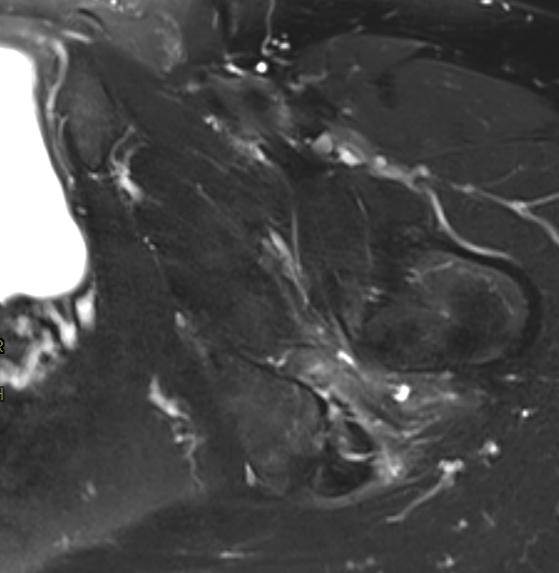

3. Ischiofemoral impingement